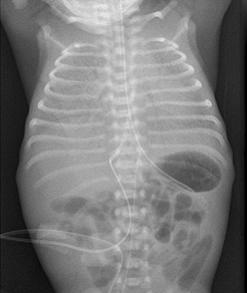

呼吸窘迫綜合症肺表面活性物質是一個混合磷脂和三個表面活性物質蛋白的物質,由Ⅱ型肺泡上皮細胞所分泌,如果缺乏肺表面活性物質,肺泡氣液交界面水分子層的滲出造成巨大的表面張力,將導致肺泡塌陷,使肺順應性下降,僵硬的肺擴張所作的功增加,這對早產兒將更為困難,因為他們的肋骨很容易變形(順應性),呼吸的用力將造成深度胸骨內陷,但進入的空氣很少,除非肋骨能很好適應肺的需求,這就造成瀰漫性肺不張。

呼吸增快,困難,呼吸呻吟常在生後立即或數小時內發生,胸骨上,下窩吸氣性凹陷,鼻翼扇動,肺不張範圍和

呼吸窘迫綜合症並非所有患呼吸窘迫的嬰兒都有呼吸窘迫的體徵,極低出生體重兒(<1000g)在出生時不能建立呼吸,因為他們的肺順應性太差,在產房時他們不能建立呼吸。